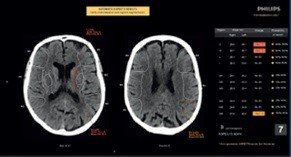

CT ASPECT Scoring

The CT ASPECT Scoring application is used to assist the clinician in the assessment and characterization of brain tissue abnormalities using CT image data. The software automatically registers images, segments and analyzes ASPECTS (Alberta Stroke Program Early CT Score) Regions of Interest (ROIs). CT ASPECT Scoring application extracts image and morphological characteristics from the ROIs. This option provides the ability to automaticlly create ASPECT scoring results and send them to PACS, as well as provides access to an interactive application used to create or modify ASPECT scoring results.